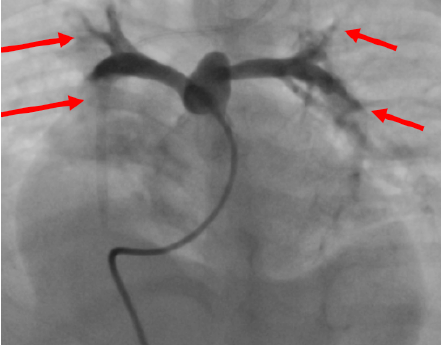

Patients were also followed up by pediatric cardiology. Two patients had ASD, and 2 patients had double superior vena cava. An endovascular procedure was performed on 1 patient due to ASD and 1 patient due to patent ductus arteriosus. Pulmonary hypertension was detected in 8 patients in the preoperative echocardiography (10-110 mm Hg). The patient with 110 mm Hg underwent cardiac catheterization; an invasive measurement was made, and pressure was measured as 37 mm Hg in the periphery (Figure 3). Pulmonary angioplasty was performed on 1 patient because of narrow exits of the pulmonary arteries (left pulmonary artery and right pulmonary artery).

Heart involvement complicates liver transplant in AGS. Severe pulmonary hypertension is a contraindication for liver transplant. Pulmonary hypertension is defined as a mean pulmonary artery pressure above 25 mm Hg as measured by right heart catheterization at rest.19 In AGS, peripheral pulmonary stenosis of varying degrees leads to pulmonary hypertension.20 In a study conducted by Zussman and colleagues, pulmonary hypertension was reduced in the acute and chronic period with 34 endovascular interventions in 9 patients.21 In a single-center study of 51 patients, Luong and colleagues showed that liver transplant can be safely performed following surgical repair in those with AGS and complex pulmonary disease.22 The mean pulmonary artery pressures of 6 patients in our study was above 30 mm Hg. Patients with high mean pulmonary arter pressure by echocardiography should have their pulmonary pressures measured with heart catheterization. In patients with AGS, the intraoperative volume imbalance secondary to peripheral pulmonary stenosis is more pronounced in the anhepatic phase. For these reasons, the patient should be closely monitored intraoperatively, and appropriate volume replacement should be made by invasive cardiac output monitoring.

Figure 3. Peripheral Pulmonary Stenosis (arrows)